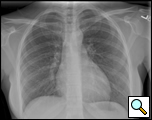

患者は29歳の女性で、喘息のワークアップ中に17歳のときに心膜嚢胞と診断されました。 最近、患者は持続的な咳を呈し、繰り返しCTスキャンで嚢胞の大きさが約6x6cmに増加していることが明らかになった(図1および図2)。 彼女の過去の病歴はWolff-Parkinson-White症候群に対して有意であった。 検査では異常は認められなかった。 嚢胞は拡大しており,有意な不安を引き起こし,持続性咳嗽に寄与している可能性があるため,切除を推奨した。 彼女の心臓専門医は、彼女のWPW症候群は手術に対する禁忌ではないと感じた。

| 図1. 術前の胸部x線。 | 図2。 胸部CTで右心腎性心膜嚢胞を認めた。 |